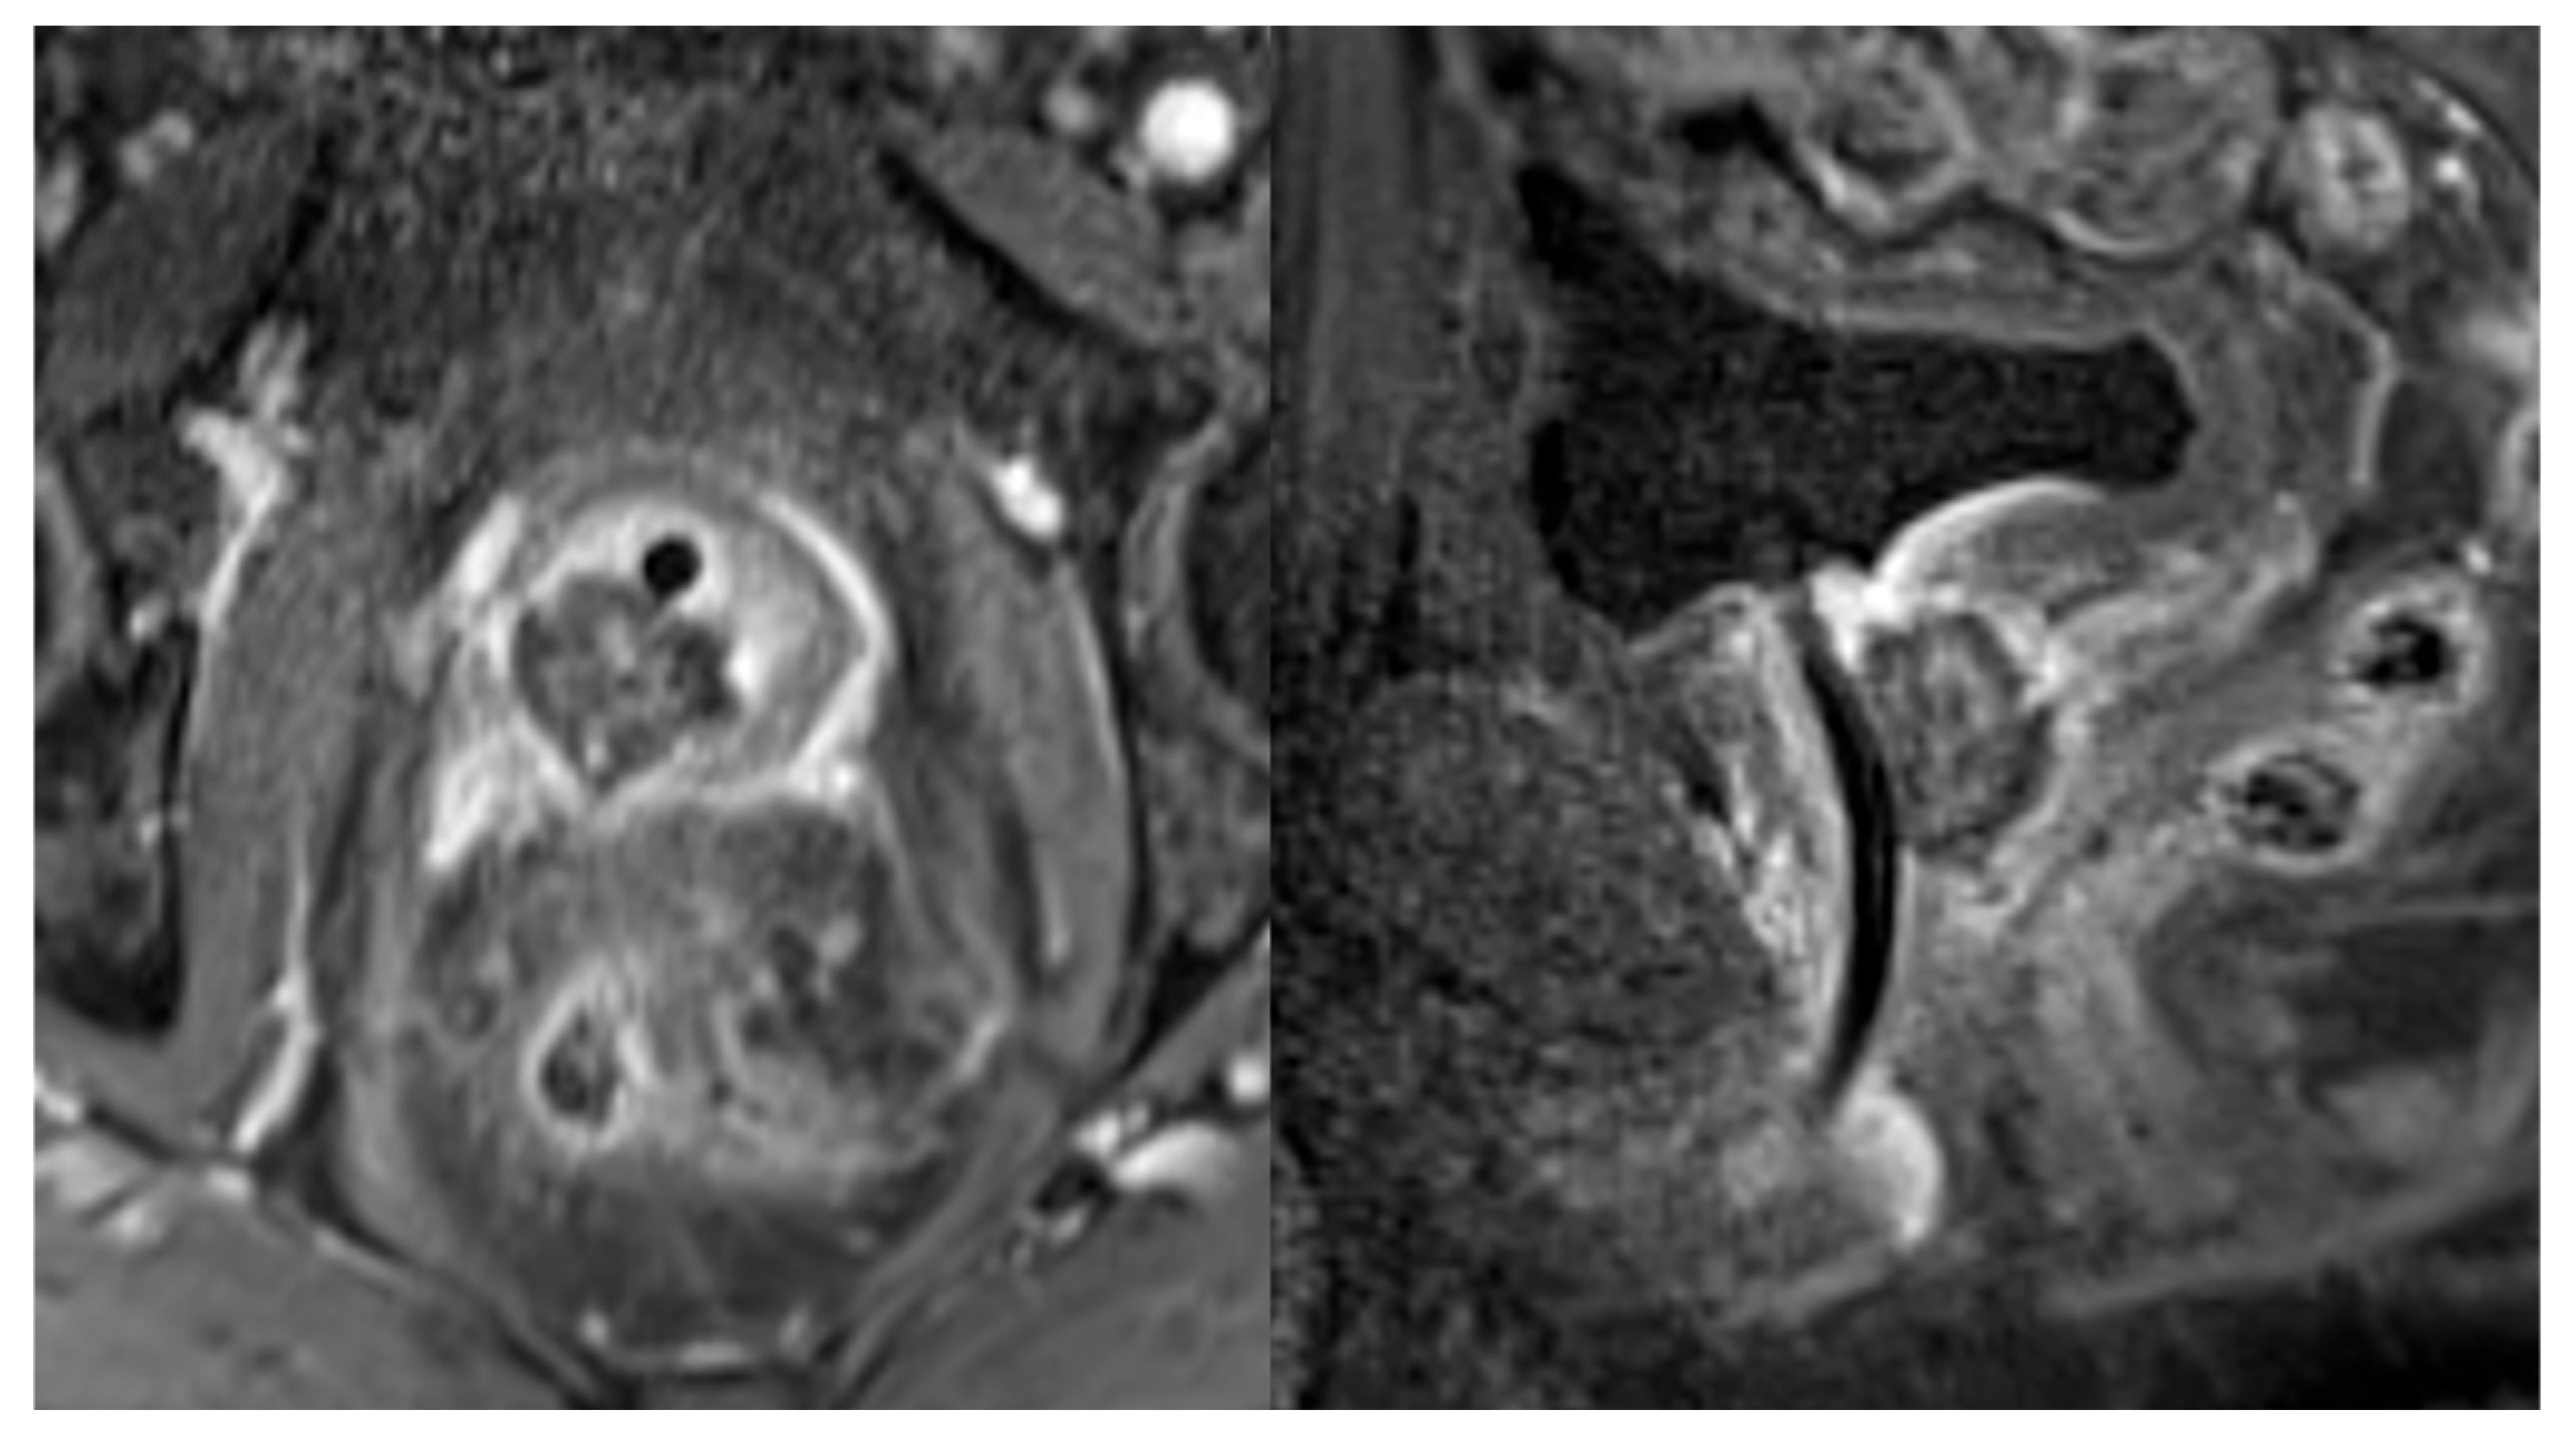

- Manenti, G.; Perretta, T.; Calcagni, A.; Ferrari, D.; Ryan, C.P.; Fraioli, F.; Meucci, R.; Malizia, A.; Iacovelli, V.; Agrò, E.F.; et al. 3-T MRI and clinical validation of ultrasound-guided transperineal laser ablation of benign prostatic hyperplasia. Eur. Radiol. Exp. 2021, 5, 41. [Google Scholar] [CrossRef] [PubMed]